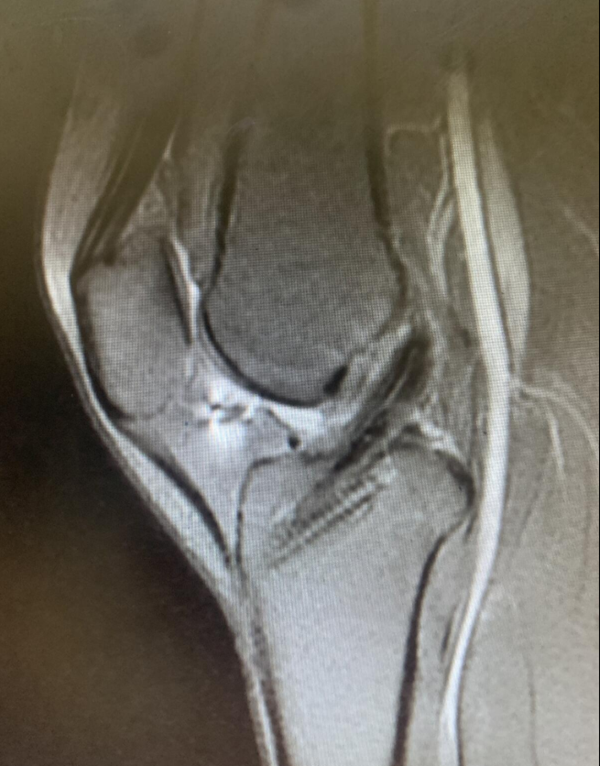

研究团队通过影像学测量发现,由术前MRI获取的外侧胫骨平台前移可用于预测急性ACL损伤后的高度旋转不稳定,外侧胫骨平台前移(≥6mm)是急性ACL损伤后高度旋转不稳定的独立危险因素,而手术治疗前空档期的长短和外侧半月板撕裂是慢性ACL损伤患者高度旋转不稳定的危险因素。

胫骨平台前移(A)外侧 和(B)内侧的测量方法

相关研究题为“Anterior Tibial Subluxation of Lateral Compartment Is Associated With High-Grade Rotatory Instability for Acute But Not Chronic Anterior Cruciate Ligament Injuries: An Magnetic Resonance Imaging Case-Control Study”,已在Arthroscopy杂志上发表。刘安医师为本文第一作者,吴浩波主任医师为通讯作者。